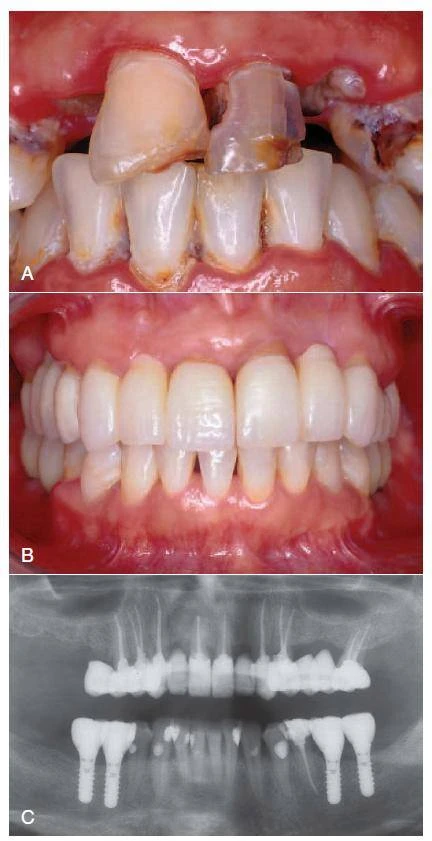

Điều trị nội nha – tạo hình và làm sạch ống tủy có giải phẫu phức tạp ( phần 1)

Giải phẫu ống tủy và bản chất đa dạng của hệ thống tủy ở người là nguyên nhân của đa…

Điều trị nội nha – tạo hình và làm sạch ống tủy có giải phẫu phức tạp( phần 2)

Điều trị nội nha - tạo hình và làm sạch ống tủy có giải phẫu phức tạp phần 2 sẽ…